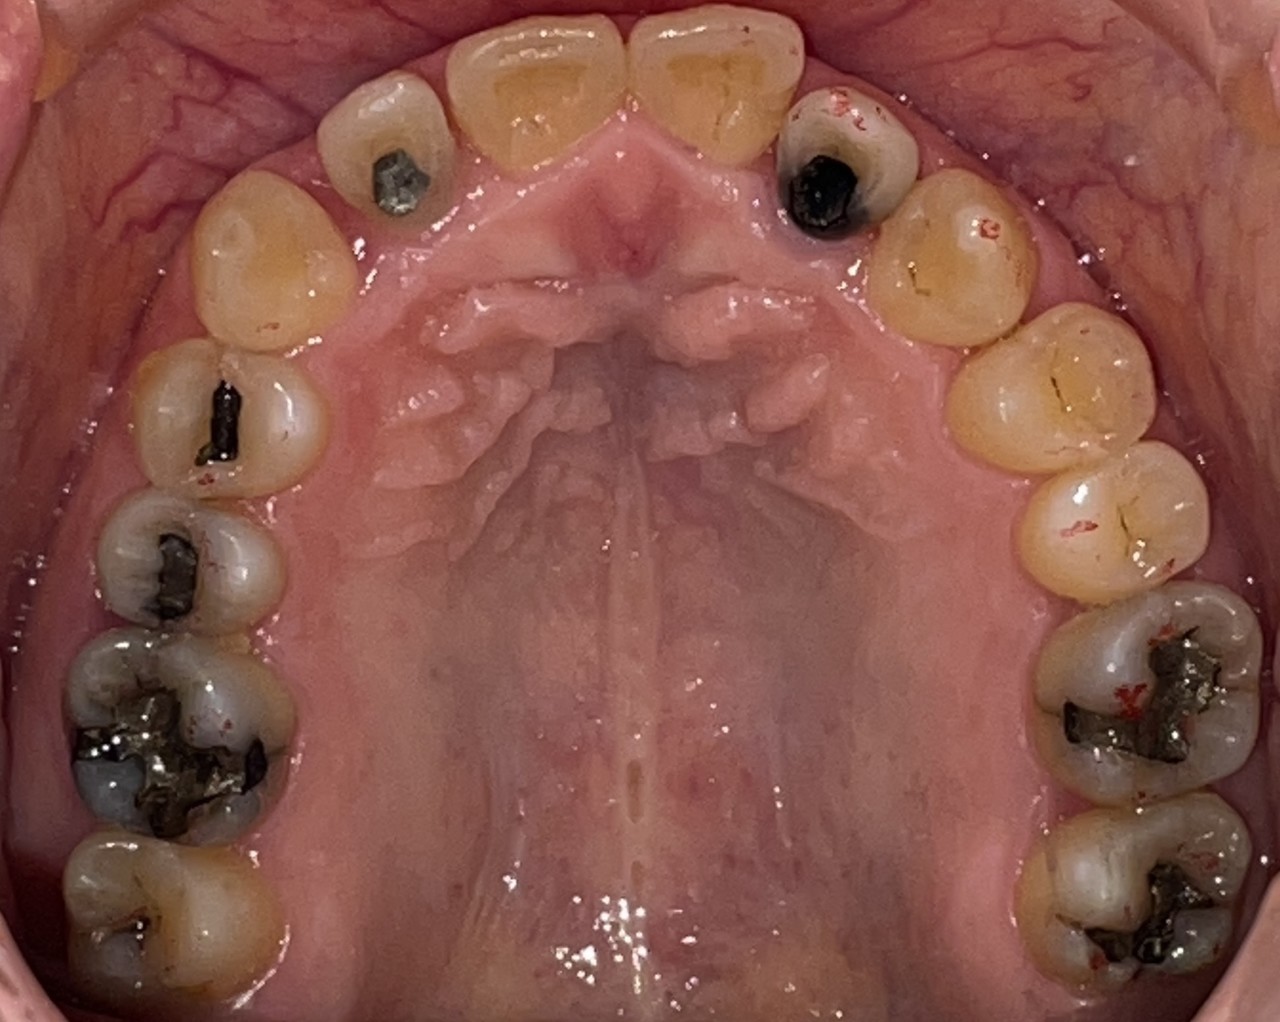

Before

After

矯正の種類 / invisalign GO

年齢・性別 / 30代女性

主訴  /  叢生 かみ合わせ

治療期間 / 17ヶ月

費用 / 簡易検査 5,000円(税別) 精密検査 30,000円(税別)

両額マウスピース 450,000円(税別)  両額リテイナー料 60,000円(税別)

※マウスピース交換時別途調節料3,000円(税別)

副作用 / 口内炎・歯の移動に伴う痛み・知覚過敏 ※数日で収まる場合が多いです

リスク / 後戻り防止の為、夜のみマウスピースで保定を指示